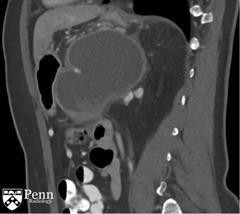

马女士, 55岁,左腰痛。腹部增强CT如下图所示。

于胰体/尾部的巨大的分叶状的囊性肿块,包绕脾动脉。其内可见一致密物在病变的内部下方与其分层。脾静脉内形成血栓,导致明显的胃肝和胃脾静脉曲张。见一假性动脉瘤起源于脾静脉的分支。

诊断:粘液性囊性肿瘤伴低度不典型增生,仅局限于胰腺,邻近慢性胰腺炎和假性囊肿形成伴囊内血栓。

CT影像学特征: 粘液性囊腺瘤呈单房或小分隔样囊性病变,边界清,呈低密度,包绕胰腺实质。囊内容物为液性密度。囊壁上可见周边的或曲线形钙化。对比增强扫描显示囊肿壁强化,并强化隔膜和壁结节。壁结节或分隔的增厚和钙化的出现强烈提示恶性病变。肿瘤末端,胰腺可能会出现如慢性胰腺炎的变化。搜寻病变局部浸润周围器官证据的重要性。 粘液性囊性肿瘤较罕见,其约占胰腺外分泌肿瘤的2.5%。 它们从良性生长缓慢的囊腺瘤(67% )到以攻击性和侵袭性粘液性囊腺癌(33%)各不相同。 有些病变是显著恶性的,但是所有的病变都被认为是潜在恶性的。常累及胰腺体尾部。 该病显着的病理特征是周围的卵巢型基质的存在。 最常见于五十至六十岁女性(女性与男性的比例为9 :1)。 患者通常无临床症状,病变可被触及或患者有症状时病变的尺寸一般大于10厘米。 由于良性肿瘤可以随时发展为浸润性癌,所有粘液性囊性肿瘤认为是手术的指征。